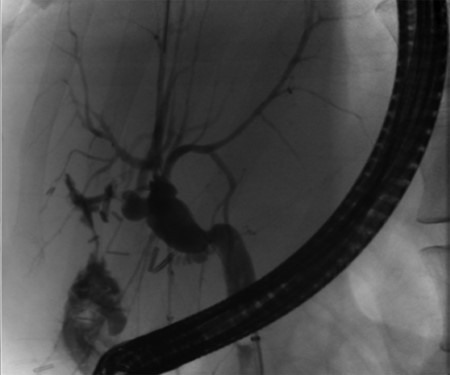

Pre-operative ERCP demonstrating compression of the common hepatic duct.

A 35-year-old female with a medical history significant for acute biliary pancreatitis status post laparoscopic cholecystectomy, presented to the surgery clinic as a new consult for a large cystic liver mass with increasing abdominal pain for 2 weeks. Patient reported suffering from severe pain in right chest, shoulder and diffuse abdominally that worsened with standing. Patient complained of inability to inspire due to pain and a 10-pound weight gain over 2 months. She confirmed decreased appetite especially with solids, nausea and emesis, alternating constipation and diarrhea, bruising, and pruritus at night. Computed tomography (CT) scan demonstrated a peripherally septated 10 x 7 cm cystic mass in the liver with intrahepatic biliary dilation (Fig. 1). The patient was referred for endoscopic retrograde cholangiopancreatography (ERCP) to establish preoperative biliary anatomy and was found to have moderate compression of the common hepatic duct managed with a right hepatic biliary endoprosthesis (Fig. 2); no obvious communication of the biliary tree with the cystic lesion was seen. Patient symptoms persisted despite optimizing with a protein-rich liquid diet; thus, the decision was made to proceed with the surgical plan for an open partial central hepatectomy. The patient was taken to the operative theater. After induction of general anesthetic, an upper midline incision was made. Inspection of the abdomen and liver showed no metastatic lesions grossly or with ultrasonographic imaging. The cyst was visible upon entry into the abdomen with no solid component to the mass in proximity to the cystic neoplasm. The second portion of the duodenum was adherent to the cyst with inflammatory adhesions and was quite boggy. A partial central hepatectomy was performed; a 3 mm biliary duct was found communicating to the cyst only with no drainage to the minimal liver parenchyma that was removed (Fig. 3). The cyst was resected en-bloc and was sent for permanent section (Fig. 4), which diagnosed the tumor as a low-grade mucinous cystic neoplasm measuring 8.5 × 7.2 × 6.4 cm. Microscopy revealed a smooth-walled, multiloculated cyst filled with a yellow-golden, semi-transparent and mucinous fluid (Fig. 5a–c). The cyst was lined by a mucinous epithelium with ovarian-type stroma. No high-grade dysplasia or malignancy was identified. The postoperative course was uneventful, and the patient was discharged on postoperative day 6. At the 4-week postoperative visit, the patient was healing well with some incisional soreness; patient was seen for removal of her biliary endoprosthesis, and ERCP found left sided intrahepatic duct biliary dilatation including a small biliary fistula from the left system (Fig. 6) with the appearance of torque on the extrahepatic biliary tree. A biliary endoprosthesis was left in place, and the patient returned for repeat ERCP 4 weeks later with resolution of all findings (Fig. 7). At present, patient remains alive with no signs of recurrence.